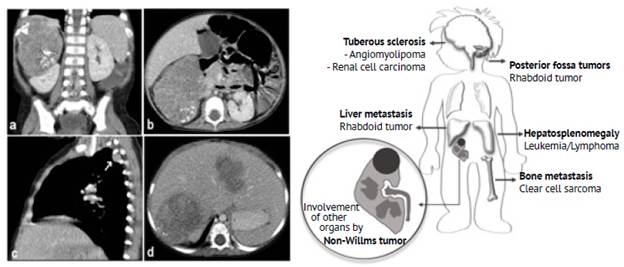

One child had a rhabdoid tumor in the right kidney; liver, lung and bone metastases were also detected at the time of diagnosis. CT scan images of this patient are shown in Figure 2.

1-year-old female with a non-Wilms tumor in the right kidney. Contrast-enhanced CT scan of the abdomen (a: coronal plane; b: axial plane) showing a solid mass of probable renal origin (right kidney) with curvilinear calcifications surrounding the tumor associated with pleural (white arrow in image c) and liver metastasis (d). According to the histopathology report, the mass was a rhabdoid tumor. The ilustration summarizes the extrarenal findings associated with the precense non-Wilms tumors.

Figure 2: 1-year-old female with a non-Wilms tumor in the right kidney. Contrast-enhanced CT scan of the abdomen (a: coronal plane; b: axial plane) showing a solid mass of probable renal origin (right kidney) with curvilinear calcifications surrounding the tumor associated with pleural (white arrow in image c) and liver metastasis (d). According to the histopathology report, the mass was a rhabdoid tumor. The ilustration summarizes the extrarenal findings associated with the precense non-Wilms tumors.

Source: Picture Archiving and Communication System of the Radiology Service of the Fundación Hospital Pediátrico La Misericordia Illustration: Own elaboration.